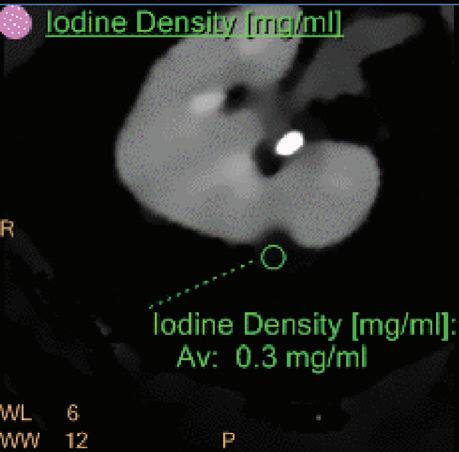

Iodine Density [mg/ml]

Also referred to as iodine map. This is a quantitative iodine image where voxel values are proportional and scaled to the iodine true concentration in units of mg/ml. Voxels without iodine content have zero iodine and hence are black (Figure 3).

Note: The algorithm includes a low bone removal threshold. Voxels with Ca content below the threshold are classified as containing iodine. The accuracy measured on a Gammex phantom with various concentrations of iodine (up to 20 mg/ml) show an iodine quantification to within 0.3 mg/ml, for both the Iodine no Water and iodine density measurements.21 In clinical conditions, an iodine concentration measurement of 0.5 mg/ml should be considered as the lower threshold for iodine uptake.

A hyperdense lesion (65 HU) is visible on the right kidney on the conventional CT images obtained after contrast enhancement. The TNC image is shown in the upper right corner. The lower row displays spectral results in the Magic Glass, from left to right: conventional CT image, VNC image, Iodine no Water image, and iodine density image. Comparison between measurements performed on the TNC (55.4 HU) and VNC images (57.6 HU) demonstrates only a minor difference between them (difference = 2.2 HU), showing that the VNC images could perfectly replace the TNC images in this clinical scenario. Iodine concentration measurements in the same region of interest show values of no more than 0.3 mg/ml which can be considered as negligible. In other words, there is no contrast medium uptake in the lesion which can thus be considered as benign. The hyperdensity is of a hemorrhagic cyst.